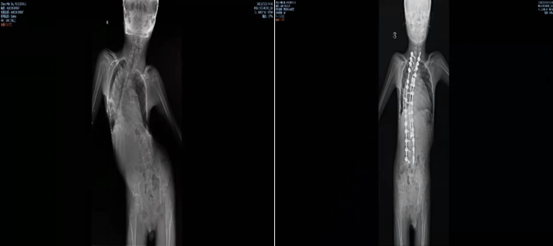

更迫切的問題是,由於肌肉無力支撐,凡凡的脊柱已經呈C型側彎,由此引發多系統功能障礙,包括呼吸功能不全及肺部感染等。

凡凡的病歷第一次被轉到北大醫院骨科是在2018年,北大醫院神經肌肉病多學科診療(MDT)團隊成立兩年。此時凡凡的脊柱明顯側彎已有六年,跑遍了北京各大醫院的骨科診室。

為凡凡會診的結果認為有必要先做脊柱矯形手術,減緩對其他臟器的壓力。但凡凡的體重實在太低,嚴重營養不良。不僅承受不了麻醉,術後的傷口縫合也困難,手術難以實現。

回國幾年後,開始有零零散散的神經肌肉病患者找到北大醫院,在罕見病聯合門診登記的1000多例SMA患者中,有近75%左右伴有脊柱畸形。李淳德開始系統地研究神經肌肉病患者的脊柱矯行治療,但真正能做手術的患者太少,20多年李淳德已慢慢積累100多臺此類手術經驗。

每月第一個週四的下午,都是北大醫院MDT團隊的會診時間。2021年,16歲的已經完全喪失行走能力三年的小樂,被確診為SMAⅢ型,伴有重度脊柱畸形,導致軀體劇烈疼痛和肺功能進一步惡化。

脊柱的扭曲,增加了尋找藥物的鞘內注射點,讓藥物順利進入到椎管內的難度。兒科接診後反覆與各科室溝通,最終決定讓小樂先接受脊柱畸形矯形手術治療。

2021年9月,李淳德在完成脊柱畸形矯正手術的同時,還要切除部分腰椎椎板,為後面注射藥物預留出骨性通道。雖然手術順利,但術後小樂的腰部無法彎曲,已經沒有同正常人一樣的解剖標誌,預留的通道也很難找到。麻醉科副主任胡曉透過超聲引導反覆摸索,尋找到預留的骨性通道,最終穿刺成功,完成國內首次SMA脊柱畸形矯形術聯合諾西那生鞘內注射。